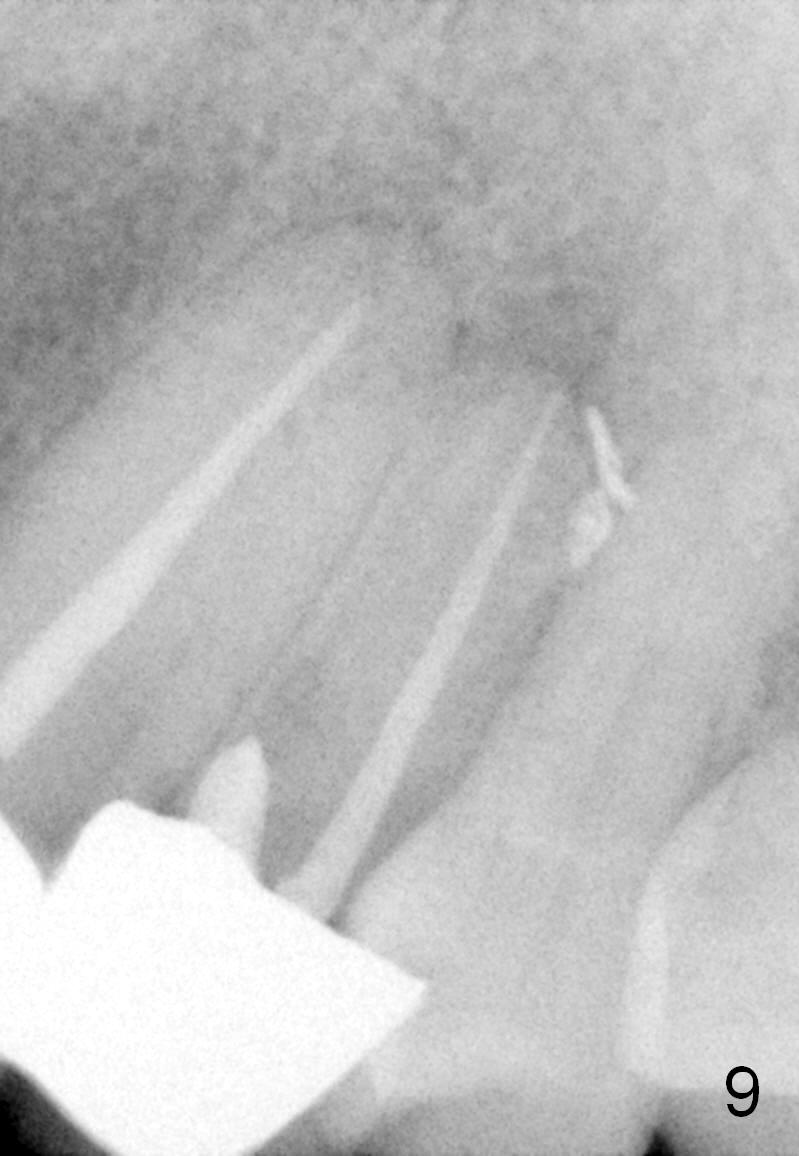

Seven months post RCT, the patient remains asymptomatic without relapse of the fistula; the periapical radiolucency apparently decreases (Fig.9). The long bridge dislodges 4 years later. The tooth #12 is extracted.